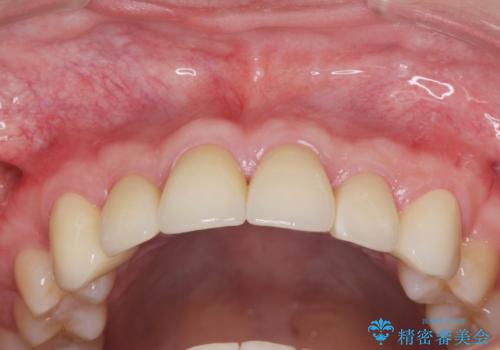

歯周外科を行い、歯ぐきの状態を整えた前歯セラミック治療

ただ、白いオールセラミッククラウンを製作・装着するのではなく、将来にわたり安定した状況を獲得するため、歯周外科を行い歯ぐきと周囲の歯槽骨の形態を整えていきます。

歯周外科を行ったことで、歯ぐきの形態や腫れが改善され、審美性だけでなく清掃性も大きく改善することができました。